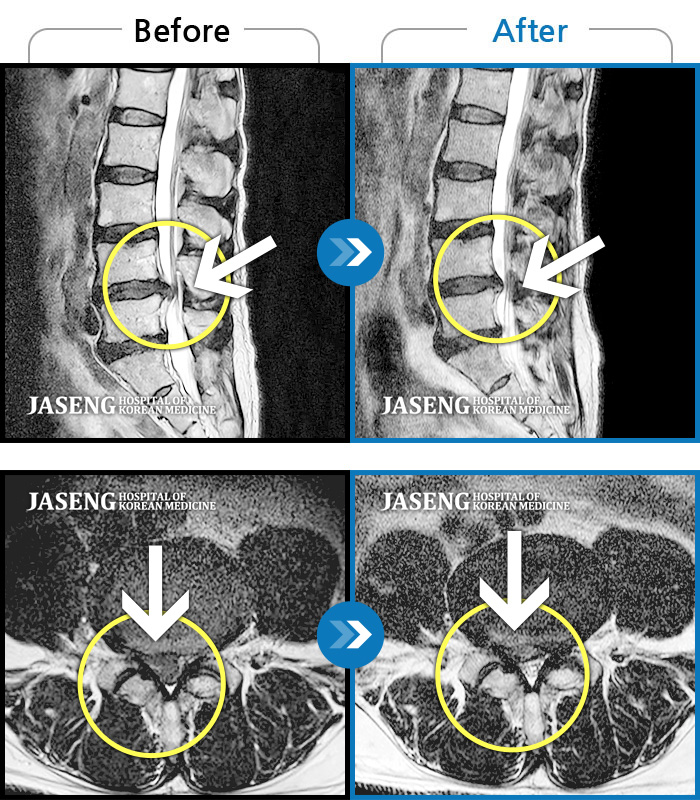

허리디스크

도움받은 사례

인천 · 조남훈 원장

재채기 하고 나서 다리에 힘이 안들어가요.

촬영시기

2021.11.10 ~ 2024.11.26

2024.12.04

조회수 443